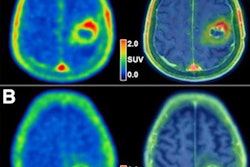

Graphical abstract. Image courtesy of the Journal of Nuclear MedicineThe researchers enrolled 30 glioblastoma patients with radiographic progression after first-line chemoradiotherapy who were planned for surgery. Patients underwent preoperative F-18 fluciclovine PET and MRI, with differences in PET radiotracer uptake between the types of tumors compared to results confirmed by biopsy lab tests.

Eighteen patients had tumor progression identified, four had mixed tumor progression, and eight patients had pseudoprogression. Patients with progression and mixed progression had significantly higher maximum standard uptake values (SUVmax) compared with patients with pseudoprogression (6.64 vs. 4.11, p = 0.009).

In addition, in patients who underwent imaging 40 to 50 minutes after radiotracer injection, an SUVmax cutoff of 4.66 provided a 90% sensitivity and 83% specificity for differentiating between tumor progression and pseudoprogression, according to the findings.